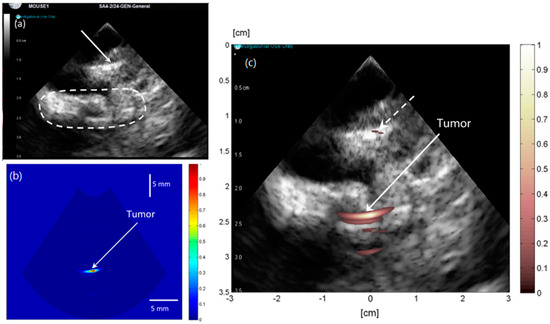

- Hariri, A.; Fatima, A.; Mohammadian, N.; Mahmoodkalayeh, S.; Ansari, M.A.; Bely, N.; Avanaki, M.R.N. Development of low-cost photoacoustic imaging systems using very low-energy pulsed laser diodes. J. Biomed. Opt. 2017, 22, 75001. [Google Scholar] [CrossRef] [PubMed]